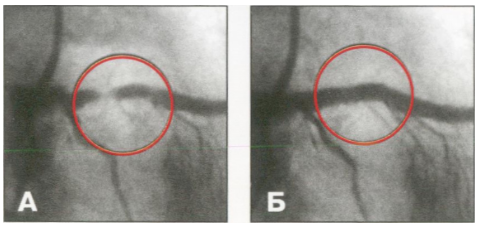

Երևանի Մխիթար Հերացու անվան պետական բժշկական համալսարանի «Հերացի» թիվ 1 հիվանդանոցային համալիրը, նպատակ ունենալով ազգաբնակչության համար ապահովելու ինվազիվ սրտաբանության ծառայության մատուցման մատչելիություն՝ սրտի ստենտավորման համար հիվանդի կողմից վճարվող գումարի չափը նվազեցնում է մինչև 1 100 000 (մեկ միլիոն հարյուր հազար) դրամ, իսկ կորոնարոգրաֆիայի արժեքը՝ մինչև 140 000 (հարյուր քառասուն հազար) դրամ: